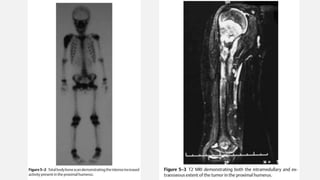

BONE SCAN/PET SCAN

• Skeletal Metastases

• Its ability to detect multicentric disease, soft tissue involvement

and viability of tumor are invaluable aids in the management of

such tumors as osteosarcoma, Ewing’s family of tumors

MRI

• The MRI demonstrates the intramedullary extent of the tumor, which is

not easily distinguished on plain radiographs.

• “Skip’’ metastases are best demonstrated on MRI

• After chemotherapy, MRI is very useful in demonstrating the reduction

in size of the soft tissue component of the tumor, which is an indication

of the effective response to preoperative chemotherapy.

EWING’S SARCOMA FEMUR

• An otherwise healthy 20-year-old male developed a sudden increasing pain in his right

femur. The pain is so severe that he is unable to walk, needs crutches, and requires

high doses of narcotics. The pain awakes him from sleep. There is no history of

associated trauma. He has not noticed any pal- pable mass nor antecedent pain in his

right femur. Of note, he had a prior anterior cruciate ligament reconstruction on his

right side, but this procedure was done in the distant past and is unrelated to any of

his pain. He has actually had excellent rehabilitation from that procedure and tolerated

the procedure well. He has had no associated fever or chills. White count and

infectious laboratory work reveal normal sedimentation rate and C-reactive protein

(CRP). Anteropos- terior and lateral femur (Fig. 19–1 and Fig. 19–2) films show a lytic

lesion of the middiaphyseal region with a sun burst periosteal reaction. Magnetic

resonance imaging (MRI) (Fig. 19–3 and Fig. 19–4) revealed a soft tissue mass with a

right peritumoral inflammatory zone associated with it. The mass measures

approximately 5 × 4 × 3 cm. Computed tomogra- phy (CT) scan shows cortical

erosions as well. A chest CT also was performed, showing no obvious pulmonary

metastases. A bone scan was ordered as well (Fig. 19–5).

Orthopedic Oncology by Ernest Conrad

Thieme